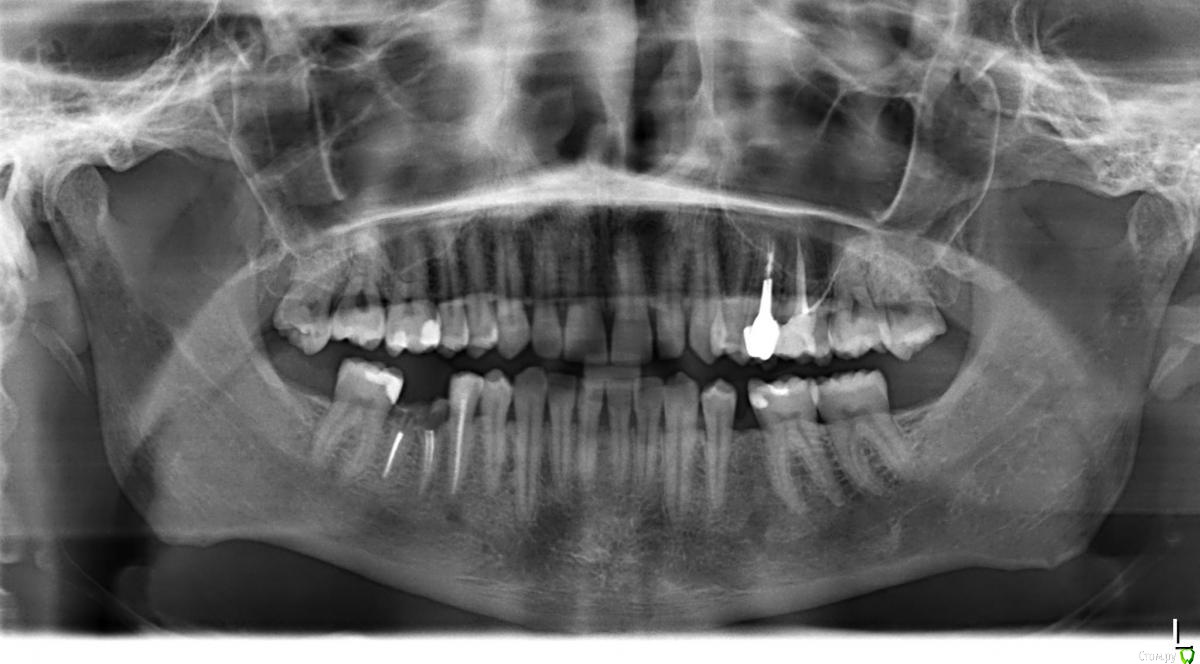

Maxkub90 Опубликовано 13 мая, 2019 Поделиться Опубликовано 13 мая, 2019 Добрый Вечер, от второго маляра остался только корень, последнюю стенку удалили пару недель назад. На снимке терапевт сказал что не может определить можно восстановить зуб или нет, я обратился к специалисту он сказал что зуб спасти не удастся. Стоит вопрос что дальше делать, с у меня частые рецедивы стоматита особенно в периоды с низким иммунитеом, сейчас прямо стоматит на стоматит, один за другим и лечатся оч долго, более 2ух недель, думаю нет сомнентй то что происходит в этом зубе влияет на их появления + естественно ужасный запах из ротовой полости. Вопросы такие-зуб спасти точно нельзя? Для того что бы определить можно ли сделать одномоментную имплантацию нужно сначала удалить зуб, что бы было виден объем кости? И можно ли проводить все эти манипуляции в период наличия стоматита во рту? Ссылка на комментарий

Maxkub90 Опубликовано 13 мая, 2019 Автор Поделиться Опубликовано 13 мая, 2019 (изменено) Забыл рентген Изменено 13 мая, 2019 пользователем Maxkub90 Ссылка на комментарий

Bier Опубликовано 13 мая, 2019 Поделиться Опубликовано 13 мая, 2019 Зуб на удаление. Верхние 8ки - тоже. Можно пересадить кстати. Верхний в нижний. Ссылка на комментарий

Bier Опубликовано 15 мая, 2019 Поделиться Опубликовано 15 мая, 2019 в вашем случае возможно сразу ставить. По снимку определяет состояние кости. Ссылка на комментарий